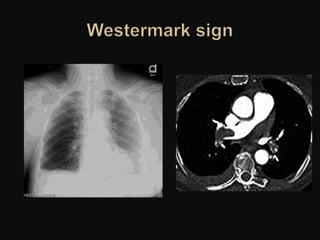

Pulmonary infarction secondary to pulmonary embolism

PH